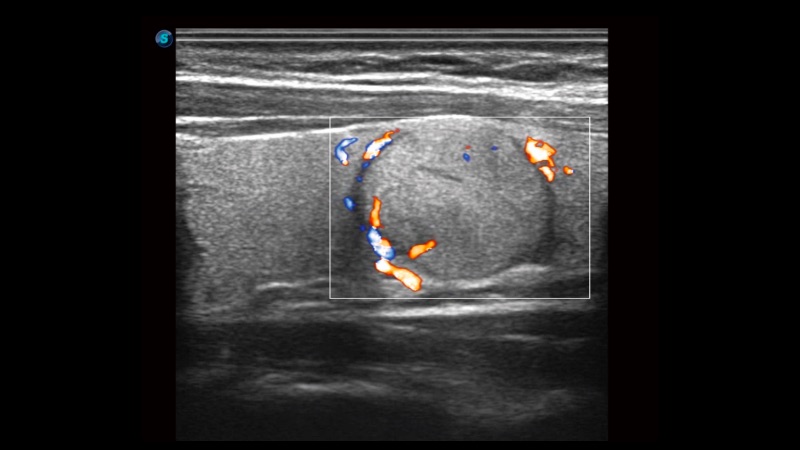

新一代微米成像技術(shù)大大提高了器官和病變的可見(jiàn)性。高清對(duì)比度分辨率將抑制斑點(diǎn)噪聲,同時(shí)保持真實(shí)的組織結(jié)構(gòu)。

自動(dòng)識(shí)別前后壁內(nèi)膜厚度,為心血管疾病早期評(píng)估提供快速準(zhǔn)確依據(jù)。